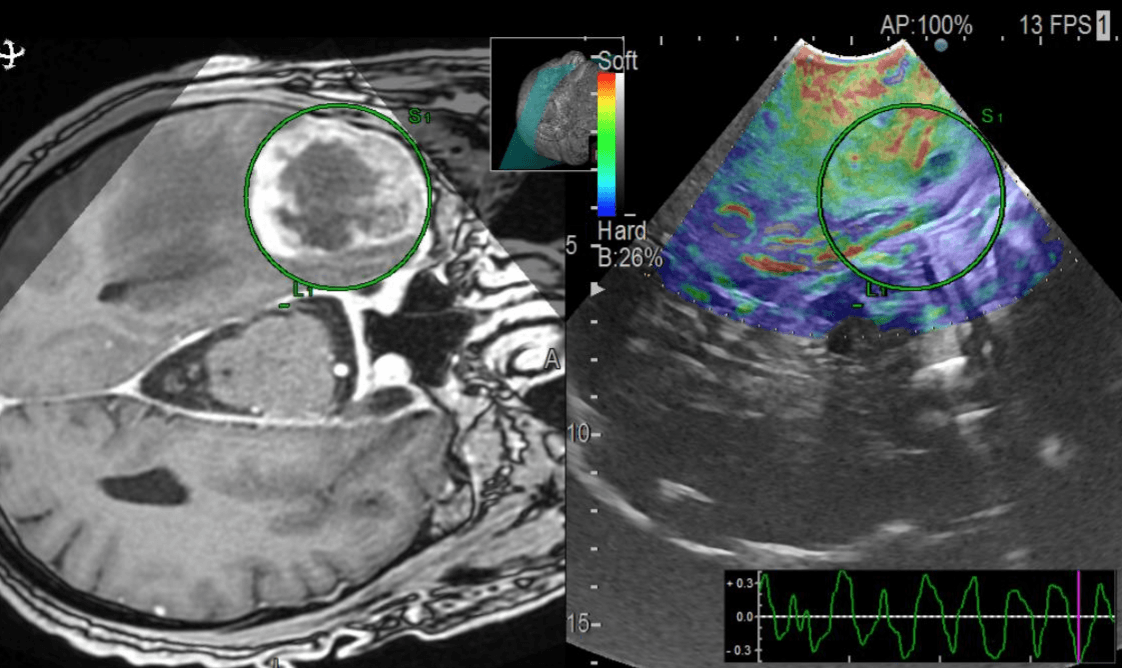

The project aims to analyze intraoperative ultrasound images of glioblastomas and develop new prediction survival models through advanced neuroimaging processing techniques and machine learning algorithms. To collect data, we promoted the creation of the first international database of intraoperative ultrasound images of brain tumors (BraTioUS-DB), in which we will collaborate with at least 6 other hospitals. At the moment we are awaiting the IRB approval of the participating centers, being the first to obtain it the Fondazione Istituto Neurologico Carlo Besta, Milano, Italy. https://www.istituto-besta.it/neurochirurgia

Predicting the survival of patients diagnosed with glioblastoma (GBM) is essential to guide surgical strategies and subsequent adjuvant therapies. Intraoperative ultrasound (ioUS) is a low-cost, versatile technique available in most neurosurgical departments. The images from ioUS contain biological information possibly correlated with the tumor's behavior, aggressiveness, and oncological outcomes. Today's advanced image processing techniques require a large amount of data. Therefore, we propose creating an international database aimed at sharing intraoperative ultrasound images of brain tumors. The acquired data must be processed to extract radiomic or texture characteristics from ioUS images. The rationale is that ultrasound images contain much more information than the human eye can process. Our main objective was to identify a relationship between these imaging characteristics and overall survival (OS) in GBM. The predictive models elaborated from this imaging technique will complement those already based on other sources, such as MRI and genetic and molecular analysis. Predicting survival using an intraoperative imaging technique that is affordable for most hospitals would greatly benefit patient management.